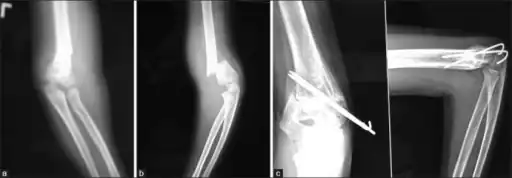

Percutaneous pinning

Percutaneous pinning are usually inserted over the medial or lateral sides of the elbow under X-ray image intensifier guidance. There is 1.8 times higher risk of getting nerve injury when inserting both medial and lateral pins compared to lateral pin insertion alone. However, medial and lateral pins insertions are able to stabilise the fractures more properly than lateral pins alone. Therefore, medial and lateral pins insertion should be done with care to prevent nerve injuries around elbow region.[3]

Percutaneous pinning should be done when close manipulation fails to achieve the reduction, unstable fracture after closed reduction, neurological deficits occurs during or after the manipulation of fracture, and surgical exploration is required to determine the integrity of the blood vessels and nerves. In open fractures, surgical wound debridement should be performed to prevent any infection into the elbow joint. All Type II and III fractures requiring elbow flexion of more than 90° to maintain the reduction needs to be fixed by percutaneous pinning. All Type IV fractures of supracondylar humerus are unstable; therefore, requires percutaneous pinning. Besides, any polytrauma with multiple fractures of the same side requiring surgical intervention is another indication for percutaneous pinning.[3]

Follow up

For routine displaced supracondylar fractures requiring percutaneous pinning, radiographic evaluation and clinical assessment can be delayed until the pin removal. Pins are only removed when there is no tenderness over the elbow region at 3 to 4 weeks. After pin removal, mobilisation of the elbow can begin.[3]